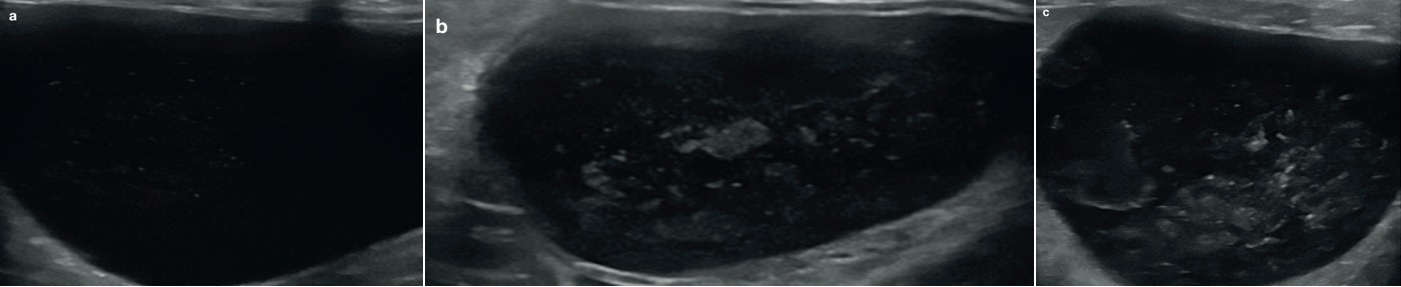

정상적인 방광의 벽 두께는 팽대되는 정도에 따라서 1.3~1.7 mm로 측정됩니다. 요관이 방광의 삼각부위로 들어가는데 요관의 유두부위가 때로는 벽 등쪽에 작은 모양으로 보입니다(그림7). 그리고 오줌이 이 유두부위를 통해서 방광으로 배출될 때 칼라 도플러로 jet 모양이 보일 수 있습니다(그림 8).

오줌은 정상적으로 무에코지만 때로는 고에코의 병소로 보이는 경우가 있습니다. 이들은 뭉쳐진 모양으로 보이나, 원위부위의 음향그림자나 연속반향 혹은 반짝이는 허상(artifacts)을 보이지 않으며, 중력 방향으로 가라앉지 않습니다. 이들은 지방뇨의 작은 방울을 나타냅니다(그림 9).